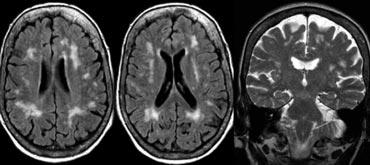

Ở hầu hết bệnh nhân VaD, có bệnh lý chất trắng lan tỏa với các tổn thương hợp lưu lớn (Fazekas 3).

Ở một số bệnh nhân này, não thất có thể giãn do teo não toàn thể và một số cũng có teo thùy thái dương trong.

Các hình ảnh là của một bệnh nhân mắc VaD, nhưng thùy thái dương trong bình thường.

Bên trái là hình ảnh của một bệnh nhân được chẩn đoán VaD.

Bệnh lý chất trắng được thấy dưới dạng tăng tín hiệu chất trắng nặng nề (giảm tín hiệu trên T1W) ở vùng quanh não thất.

Ngoài các thay đổi mạch máu này, còn có MTA.

Có thể bệnh nhân này mắc cả VaD và AD, một phát hiện thường gặp ở nhiều bệnh nhân cao tuổi.

Các dấu hiệu này cần được mô tả riêng biệt vì có thể có hệ quả điều trị.